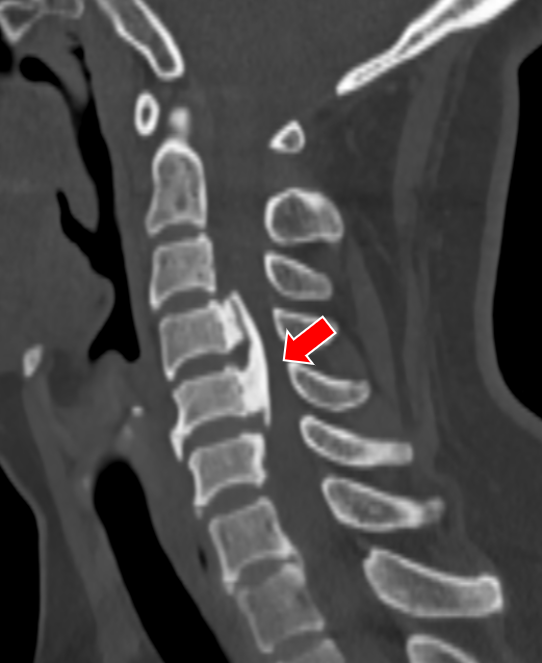

沈阿姨今年58岁,原本正是准备享受生活的年纪,但在今年5月,困扰了她长达4年的颈肩痛明显加重了。短短一周时间,沈阿姨的右上肢就出现了麻木感,吃药、理疗完全无法缓解,症状发展很快,于是立刻来我院骨科就诊。颈椎CT上可以清晰看到,她C4-5的椎间盘明显向右后方突出,椎间隙后缘骨赘增生,导致神经根受压。

(颈椎CT提示患者C4-5的椎间盘突出(右后方),椎间隙后缘骨赘增生)